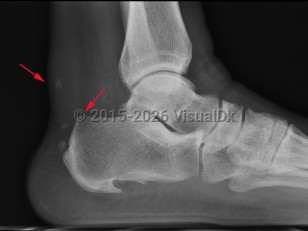

Haglund deformity is enlargement of the posterosuperior tuberosity of calcaneus. Retrocalcaneal bursitis is inflammation of the space between the anterior aspect of Achilles tendon and posterior aspect of calcaneus.

Middle-aged or elderly patients are more likely to present with insertional Achilles tendonitis. Young, active patients are more likely to present with Haglund deformity or retrocalcaneal bursitis, which are often components of Achilles tendonitis.